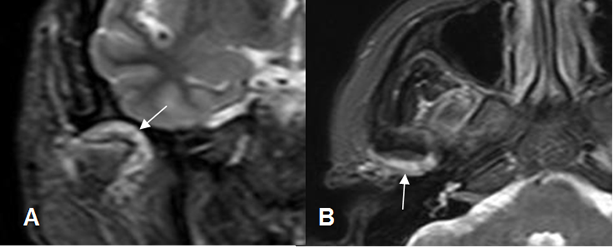

Fig 9. Disco luxado, que no reduce.

A: RM GE sagital oblicuo con boca cerrada. Disco con alteración de su morfología y señal, desplazado anteriormente.

B: RM GE sagital oblicuo con boca abierta. El disco persiste desplazado anteriormente.